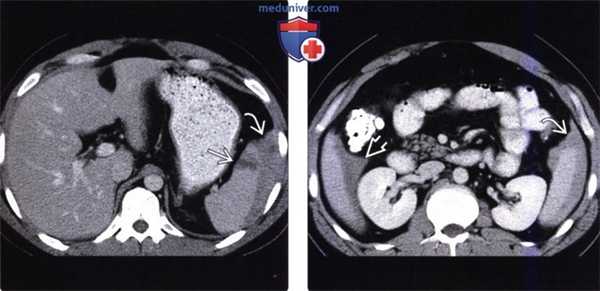

(Слева) На аксиальной КТ с контрастным усилением у молодого мужчины, пострадавшего в ДТП, определяется разрыв паренхимы селезенки с наличием сгустка крови высокой плотности, прилежащего к ее краю.

(Справа) На аксиальной КТ с контрастным усилением у этого же пациента также определяется сгусток крови, прилежащий к краю селезенки (типичный «сторожевой сгусток»), наряду со скоплением геморрагической жидкости меньшей плотности, более однородной структуры, во всех отделах брюшной полости. Заживление произошло самостоятельно, без хирургического вмешательства.